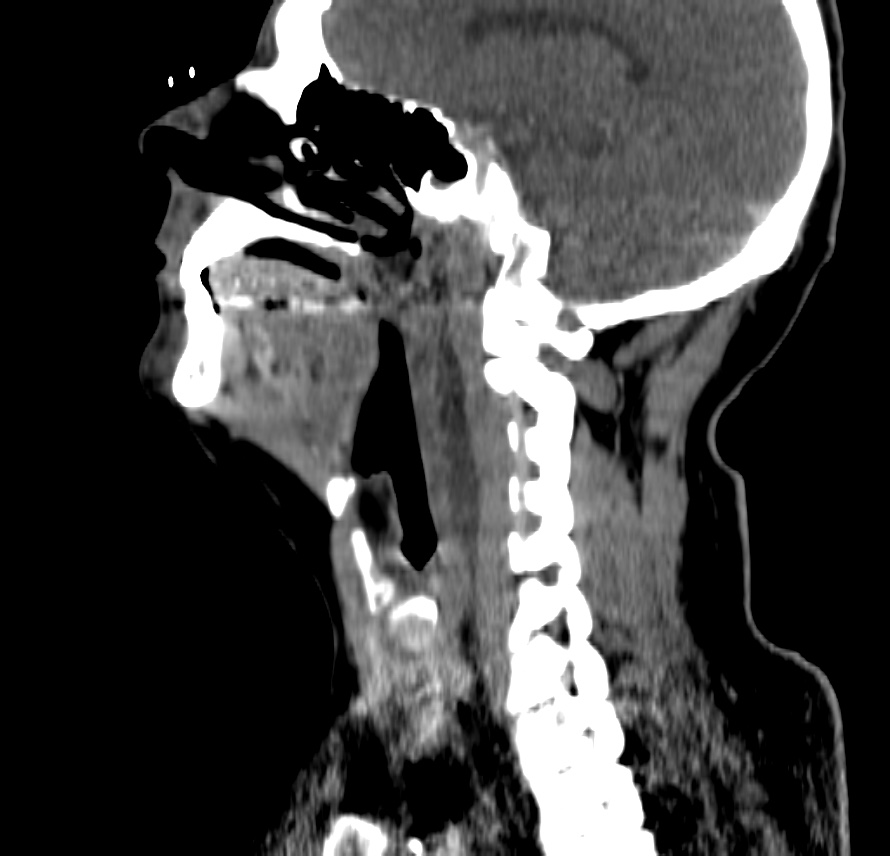

ESPACIO RETROFARÍNGEO:

En el adulto, este espacio contiene fundamentalmente grasa, mientras que los niños (hasta los 6 años) pueden presentar ganglios. Suele darse en niños e inmunocomprometidos por diseminación vía linfática de infecciones de tejidos adyacentes. La afectación de este espacio es muy importante porque puede extenderse al mediastino, normalmente entre los niveles D1 – D6

Clínica: fiebre, disfagia y dolor cervical que aumenta con los movimientos de rotación y flexión-extensión.

Hallazgos:

- Colección líquida con realce periférico en anillo, que ocupa y expande la retrofaringe, con o sin gas.

- Cuando se observa edema, fluidos o inflmación con aumento del espesor, hay que seguir caudalmente el espacio retrofaríngeo en indicar el punto donde vuelve a ser normal o hasta observar si existe o no afectación del mediastino.

- Determinar si existen complicaciones como: extensión al mediastino, compromiso de la vía aérea, asociación de espondilodiscitis o absceso epidural y compromiso del espacio carotídeo, que puede ocasionar trombosis de la vena yugular interna (Síndrome de Lemierre).